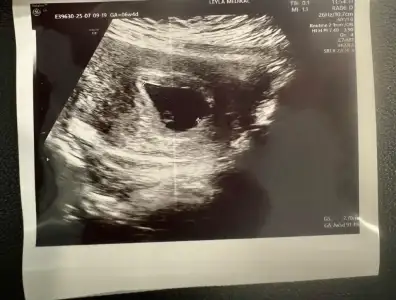

6 haftalik karından ultrasyon tahminde bulunabilir misiniz

Eklentiler

• IMG_20250312_112835.webp

IMG_20250312_112835.webp

31,3 KB · Görüntüleme: 70

• IMG_20250312_094215.webp

IMG_20250312_094215.webp

21,9 KB · Görüntüleme: 58

• IMG_20250312_094132.webp

IMG_20250312_094132.webp

44,2 KB · Görüntüleme: 73